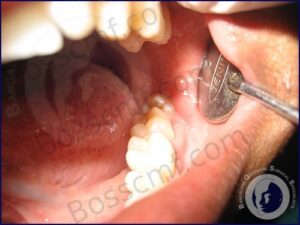

Wisdom teeth or third molars are the last teeth to erupt in the mouth. “inadequate space sometimes leads to partial or total lack of eruption resulting in “impacted” wisdom teeth. These teeth can cause several problems including local infection and damage to adjacent teeth and hence are removed, commonly by means of a small surgical procedure which usually involves drilling of surrounding bone.